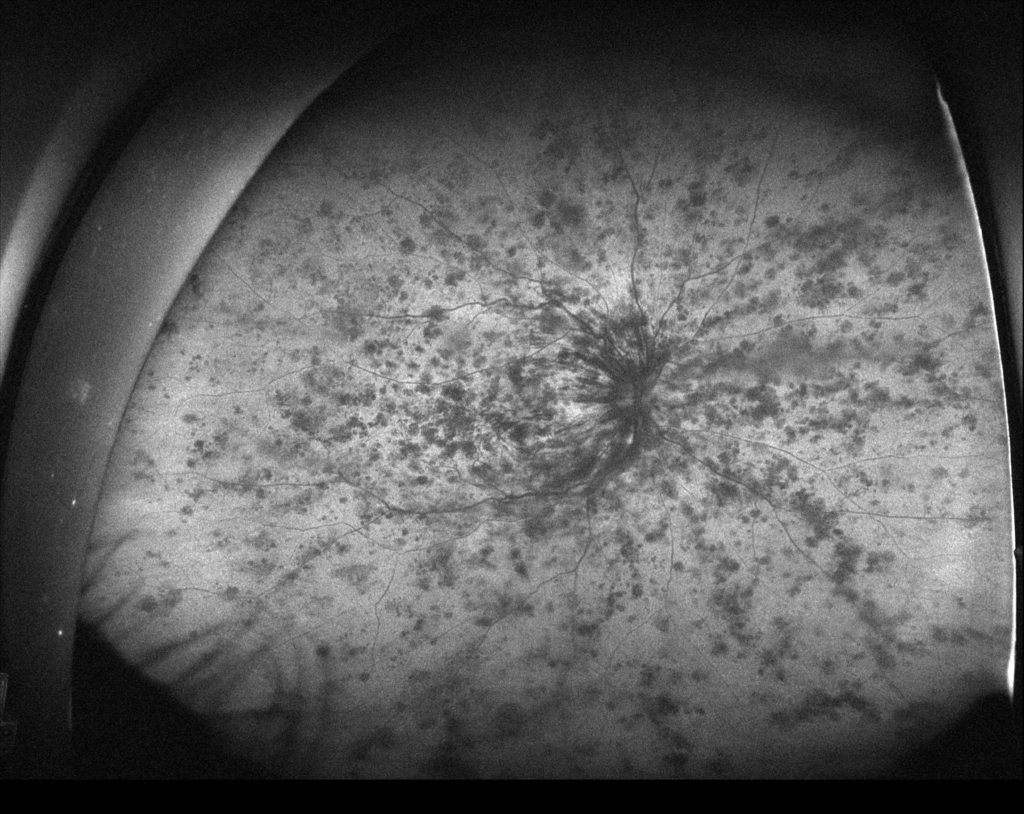

抗VGEF(ラニビズマブ)の硝子体注射2日後。